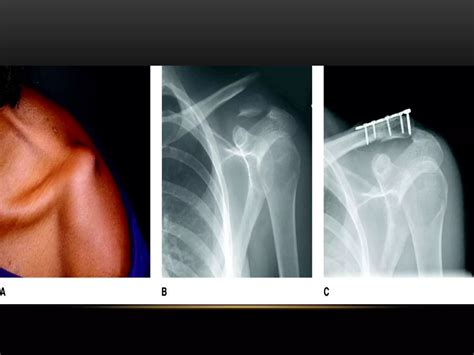

Clavicle Fracture Treatment